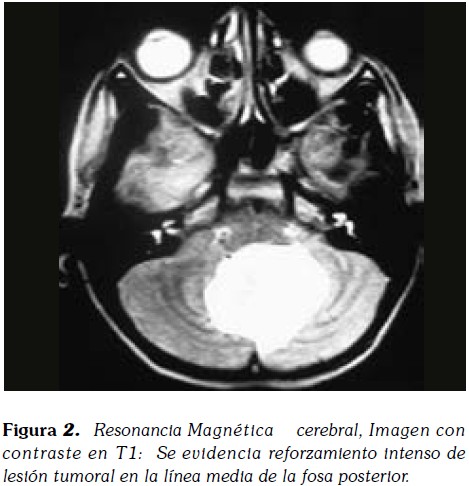

Paciente masculino de 13 años de edad, quien acudió al servicio por presencia de cefalea continua, con aumento de los síntomas en los últimos 4 meses. Asociado refería emesis y ataxia. Padres refieren disminución de la concentración y reporte de bajo desempeño escolar en el último ano. Paciente fue remetido del servicio de neurología pediátrica al cual fue consultado por bajo rendimiento escolar e hiperactividad. La resonancia magnética (RM) (Figura 1) mostró una lesión de masa bien definida, línea media de la fosa posterior, predominantemente hipointensa en T1 y heterogéneamente hiperintensa en T2 con realce intenso de estudio post contraste (Figura 2). Medía 4.3x3.5 cms de tamaño, comprimiendo el cuarto ventrículo que conduce a la dilatación leve de ventrículos laterales, tercero y cuarto. La masa apareció a extenderse a lo largo de la superficie ventricular de la protuberancia y en la cisterna interpeduncular y fue diagnosticado clínicamente y radiológicamente como meduloblastoma. Posterior craneotomía con enucleación completa de la lesión se realizó junto con la citología intraoperatorio.

La tomografía computarizada (TC) pueden mostrar calcificación, hidrocefalia obstructiva, y el contraste uniforme en aumento, pero la RM es necesaria para el diagnóstico. La tumoración es hipo o isointenso en T1 y mejora la densidad y de manera uniforme después de la adición de gadolinio. La TC y la RM muestran realce intenso uniforme después de la inyección de contraste los medios de comunicación debido a su falta de sangre y la barrera del cerebro. La histopatología de estos tumores puede ser de cualquier tipo (predominantemente fibroso, fibroblástica, meningotelial, o psamomatoso) tal como se define por la Organización Mundial de la Salud y la Clasificación 's de meningiomas. Generalmente, se diagnostican con base en características morfológicas solamente.